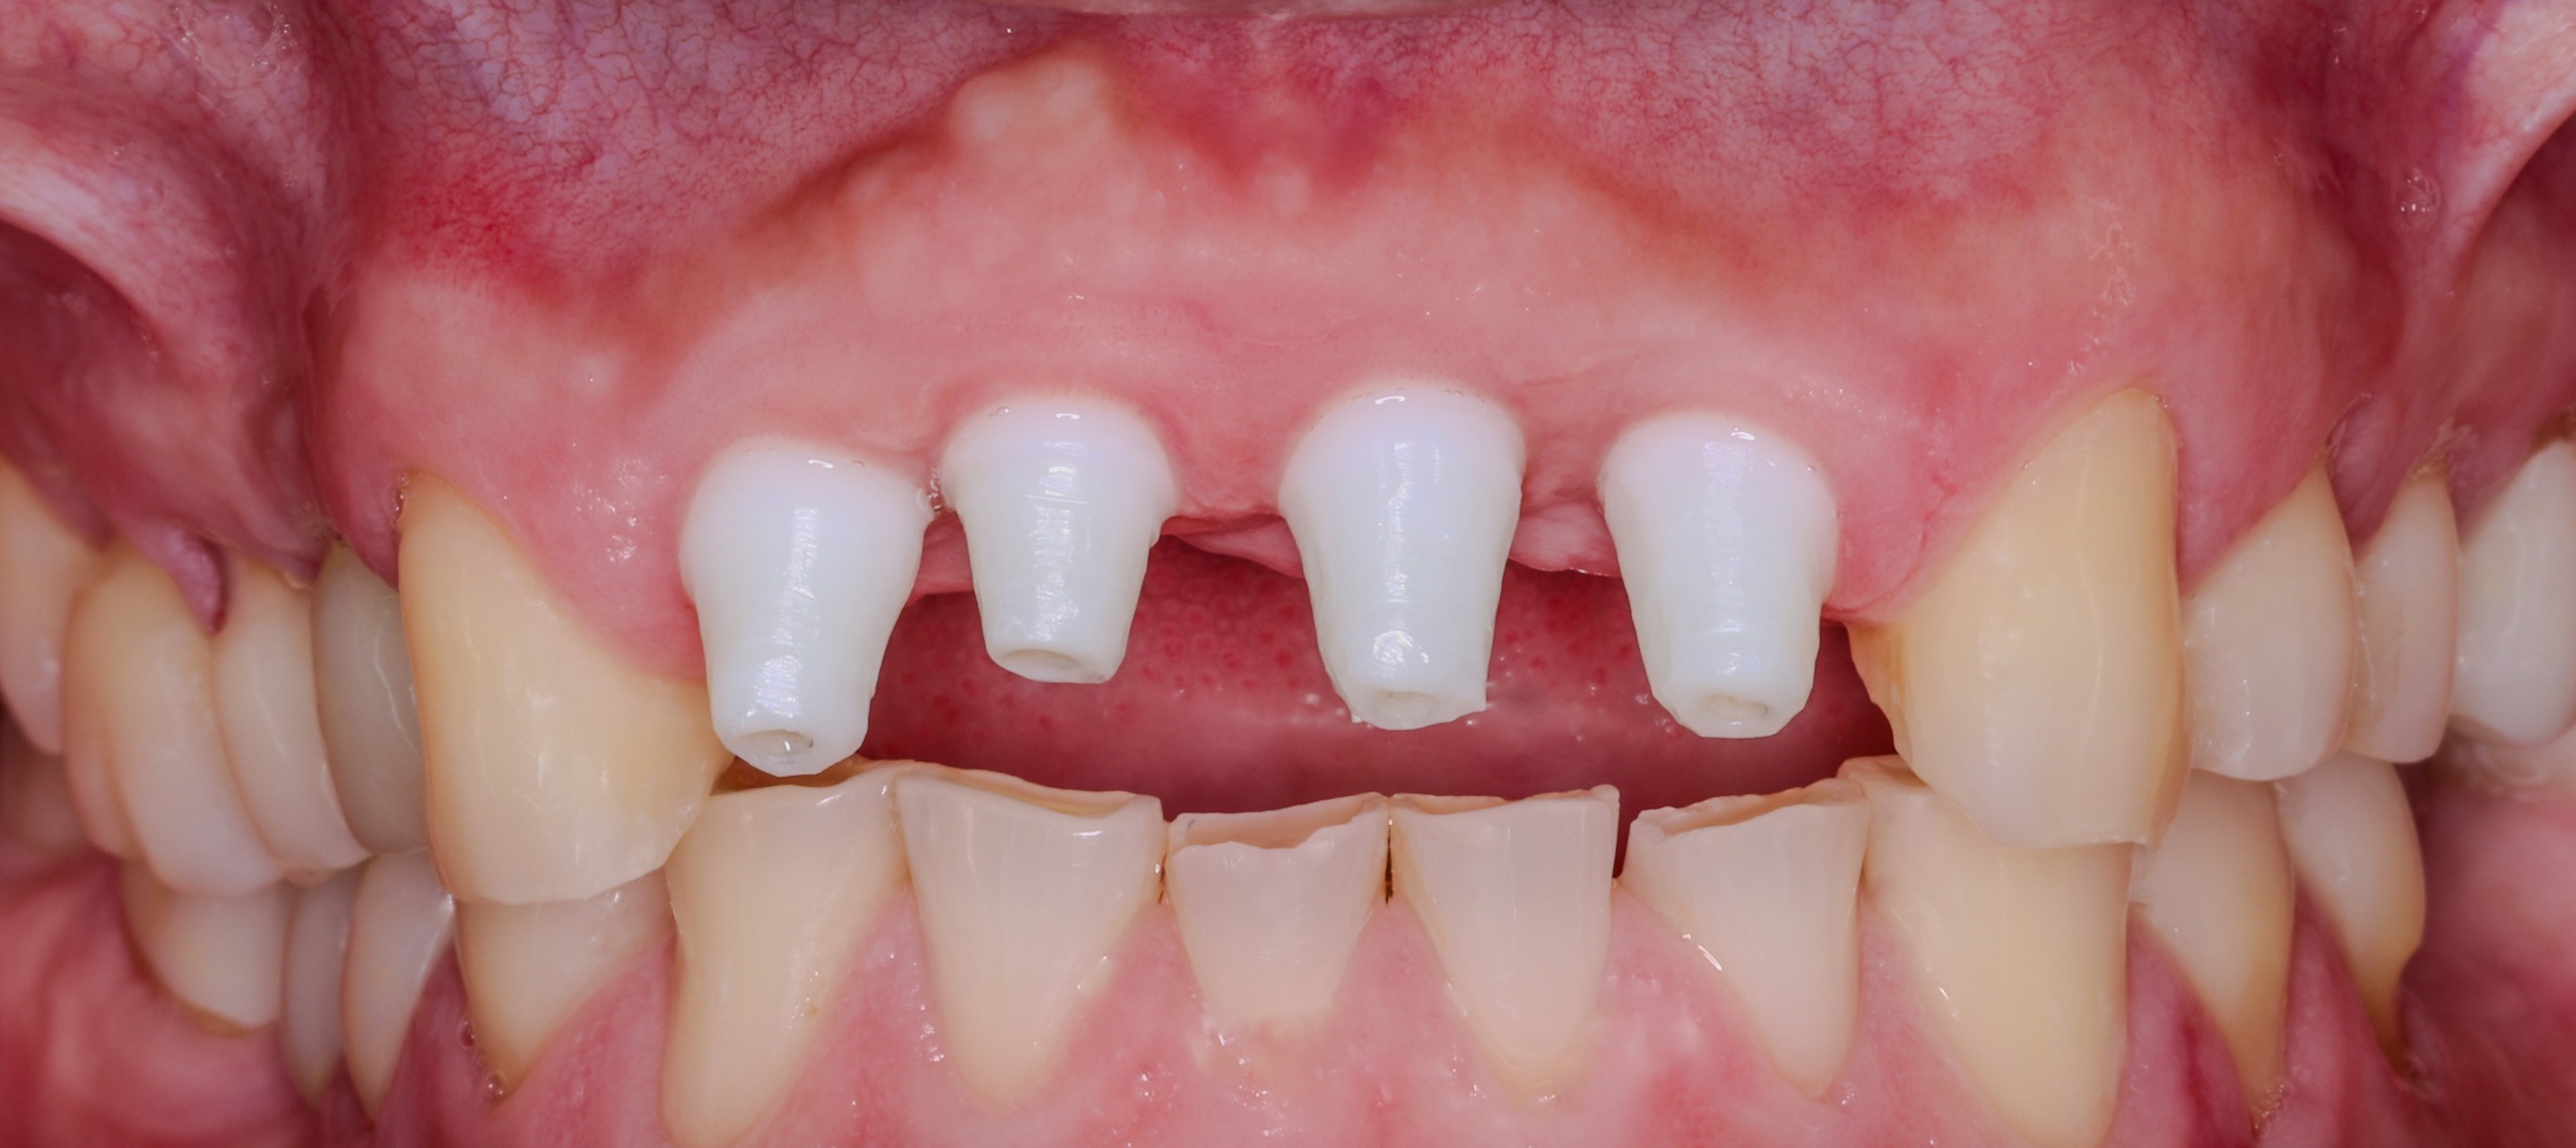

March 06, 2024Placement of four maxillary anterior implants (#7–10 region) into regenerated bone with careful three-dimensional positioning and provisionalization to support soft tissue shaping.

June 08, 2024Follow-up visit confirming implant stability, soft tissue healing, and refinement of the anterior emergence profile in preparation for final restorations.